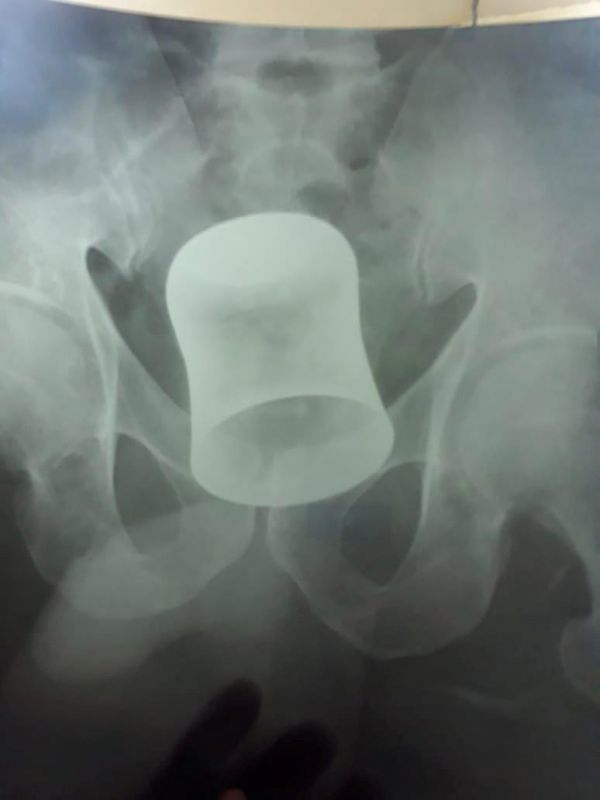

62-летний охранник по имени Рамдин подвергся вооруженному нападению. Грабители похитили денежные средства в размере $700 и засунули пожилому мужчине в задницу металлическую чашу. В ходе истязаний индус потерял сознание и многого не помнил. Через 10 дней он обратился в больницу Рама в городе Канпур, Индия, с сильными болями в области живота. Мужчине провели ультразвуковое сканирование, чтобы выяснить причину болей, и были поражены, увидев стальной стакан, застрявший в области живота. Изначально врачи пытались удалить чашу через сам анус, но через час, несмотря на все их усилия, не смогли этого сделать. Кубок был удален через желудок после двух часов кропотливой инвазивной операции.